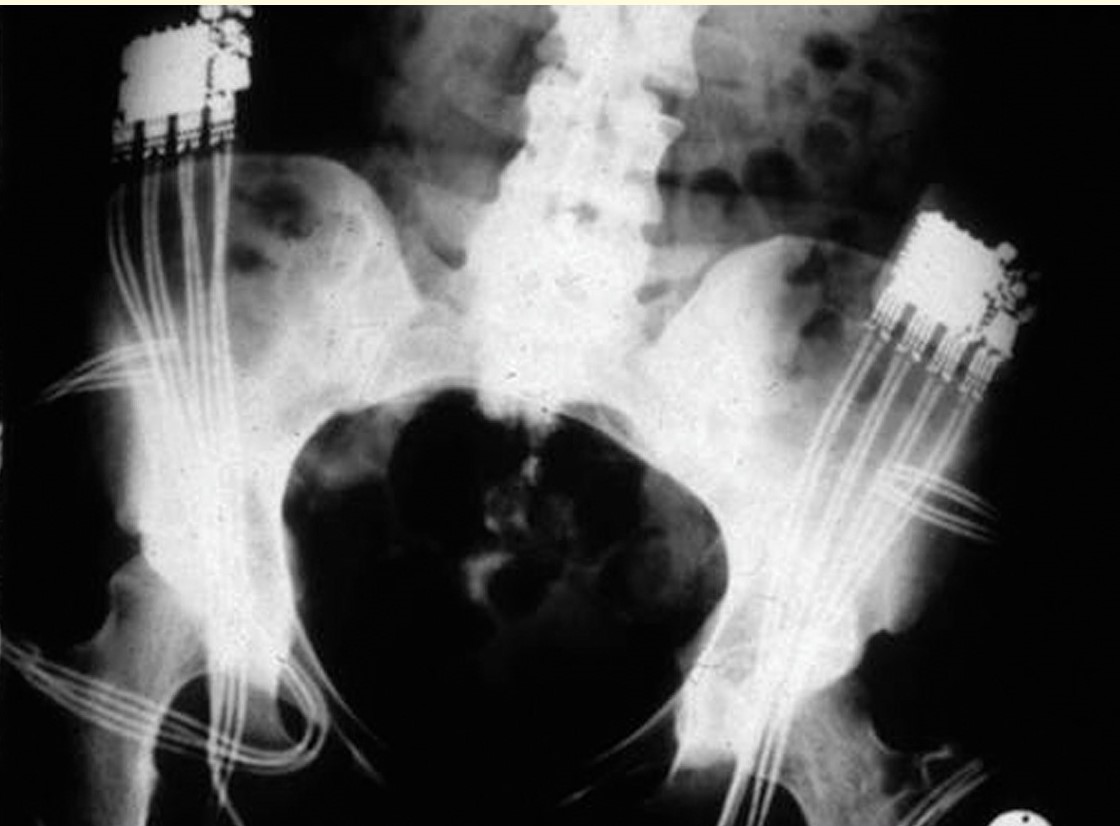

We design and evaluate novel technological solutions and neurorehabilitation approaches to restore altered or missing sensorimotor functions. In this frame, we develop various external and implantable devices for experimental studies and clinical investigations. Moreover, we are spearheading muscular training research following upper or lower motor neuron disorders by functional electrical stimulation, assisting mobility, as well as neuromodulation of altered sensorimotor function by transcutaneous and epidural electrical spinal cord stimulation.

Since the early 1980ies we have contributed to neuroprosthetics by investigating new applications and developing various technologies like stimulation and sensor systems. The use of multi-channel implants as respiratory- and leg pacemakers, the development of surface stimulators to prevent muscle atrophy during long-term flights onboard the MIR space station are only examples of our innovative work during the last decades. A significant achievement was the finding that long-term denervated muscles could be reactivated and their function partially restored by FES training. Basic understanding of denervation, technological innovations, and new rehabilitation strategies were part of the RISE project, in cooperation with international partners.